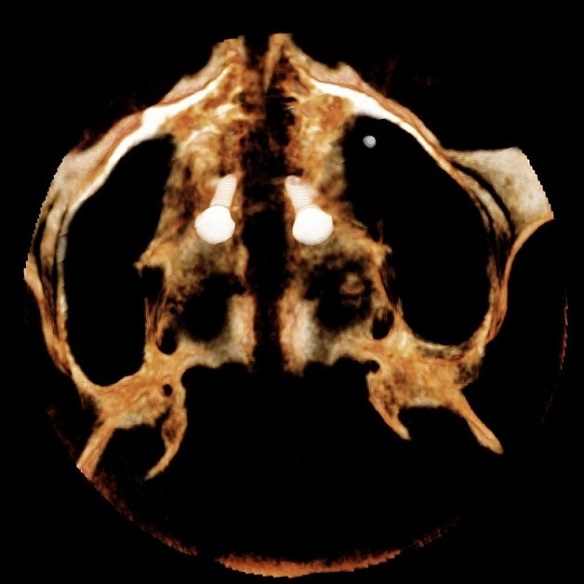

Rzut osiowy podniebienia po ekspansji u osoby dorosłej – widoczne równoległe rozejście się szwu podniebiennego na całej długości: